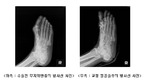

- 내성발톱 • 무지외반증 등 엄지발가락 질환, 무릎허리 등 2차 통증 유발 - 좁고 뾰족한 신발 • 굽 높은 하이힐 등 잘못된 신발착용도 주 원인 - 족욕, 마사지, 발가락스트레칭 등 평소 세심한 발관리로 예방가능 과거 미국에서는 흑인 노예들이 달아나다 잡히면 다시 달아나지 못하게...